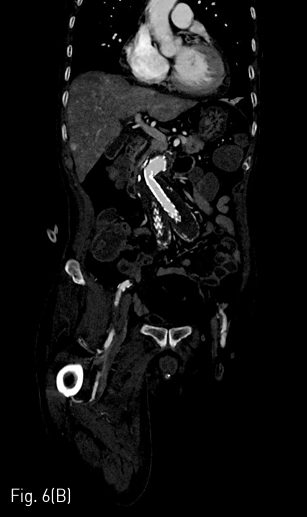

(A,B) CT angiography obtained 1 month later the procedure shows patent intraluminal space of bilateral iliac limb graft.

Fig 6B

시술 1개월 뒤 시행한 조영증상 CT에서 양측 장골 분지 인조혈관 내강은 잘 유지되었다(Fig. 6A&B).